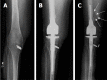

This case report describes in detail an erosive distal diaphyseal pseudotumor that occurred 6 years after a complex endoprosthetic hinge total knee arthroplasty (TKA). A female patient had conversion of a knee fusion to an endoprosthetic hinge TKA at the age of 62. At her scheduled 6-year follow-up, she presented with mild distal thigh pain and radiographs showing a 6-7 cm erosive lytic diaphyseal lesion that looked very suspicious for a neoplastic process. An en bloc resection of the distal femur and femoral endoprosthesis was performed. Histologic review showed the mass to be a pseudotumor with the wear debris emanating from within the femoral canal due to distal stem loosening. We deduce that mechanized stem abrasion created microscopic titanium alloy particles that escaped via a small diaphyseal crack and stimulated an inflammatory response resulting in a periosteal erosive pseudotumor. The main lesson of this report is that, in the face of a joint replacement surgery of the knee, pseudotumor formation is a more likely diagnosis than a neoplastic process when encountering an expanding bony mass. Thus, a biopsy prior to en bloc resection, would be our recommended course of action any time a suspicious mass is encountered close to a TKA.